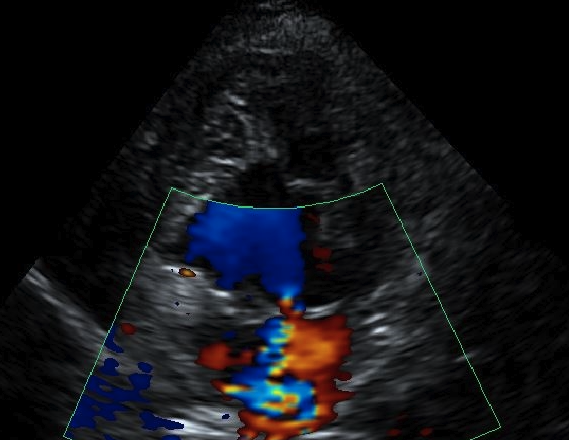

오늘은 강아지 유선종양 케이스에 대해 포스팅해보겠습니다. 12살, 말티즈 딸*가 호흡곤란으로 내원하였습니다. 호흡곤란 증상으로 예상할수있는 몇몇 호흡기 질환과 심장병 등을 예상해보았습니다. 엑스레이 검사에서 정상적인 폐가 거의 보이지 않고 흉수가 차 있는 모습을 보여 즉시 흉수를 뽑아주었습니다. 뽑은 흉수의 양은 280ml 정도였습니다. 흉수천자덕분에 딸*의 호흡은 한결 편안해졌지만, 의료진의 손길은 더욱 바빠졌습니다. 흉수의 원인을 찾아야하거든요. 심장병이 있는경우 특히 오른쪽 심장에 문제가 발생하는 우심부전의 경우에도 흉수가 생길 수 있습니다. 딸*의 경우 왼쪽심장에 판막변성으로 인한 심질환은 있었으나 오른쪽 심장은 비교적 건강한 편이 었습니다.

흉수검사 결과 흉수 내에서 악성세포가 확인되었습니다. 그렇다면 원발성 종양은 어디에 있었을까요.. 12살 딸*는 대략 7살경에 중성화수술을 한 중성화된 여자아이입니다. 몸 밖, 특히 배 부분에 종양을 주렁주렁 달고있었어요. 한군데가 아니라 여러군데입니다. 다행히 복부초음파 검사상 복강 내에서 다른 종양을 가진 장기는 확인되지 않았습니다.